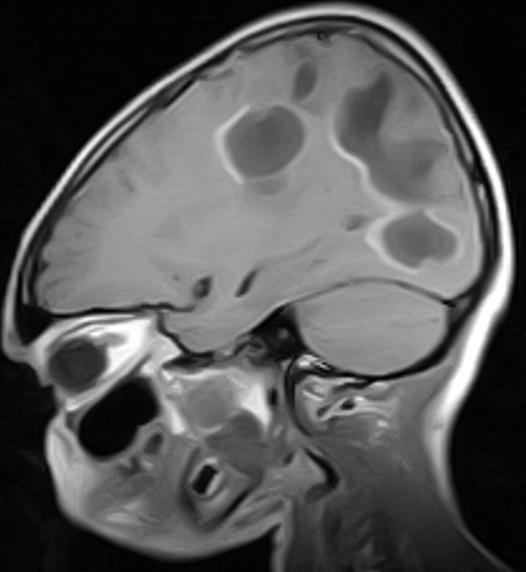

A Primary Angiitis of the Central Nervous System (PACNS) is ill-defined, complex and rare in children. Clinical presentation is variable, diagnosis is challenging and it is life-threatening but treatable. The index case is a 9-year old male who presented with progressively slurred speech, progressive weakness of the limbs, hemifacial weakness and vomiting. There were no clinical or laboratory features of systemic vasculitis. Neuroimaging showed multiple subacute infarcts in both cerebral hemispheres. He responded well to immunosuppressive therapy. The case report aims to underscore the need for high index of suspicion, early neuroimaging for progressive nonspecific decline in neurologic function and the treatable nature of the condition if diagnosis is made early.

儿童中枢神经系统原发性血管炎(PACNS)的定义不明确、情况复杂且罕见。临床表现多样,诊断具有挑战性,它会危及生命但可治疗。索引病例是一名9岁男性,表现为逐渐加重的言语不清、肢体进行性无力、面瘫和呕吐。没有系统性血管炎的临床或实验室特征。神经影像学显示双侧大脑半球有多个亚急性梗死灶。他对免疫抑制治疗反应良好。该病例报告旨在强调高度怀疑的必要性、对神经功能进行性非特异性下降进行早期神经影像学检查以及如果早期诊断该疾病具有可治疗性。